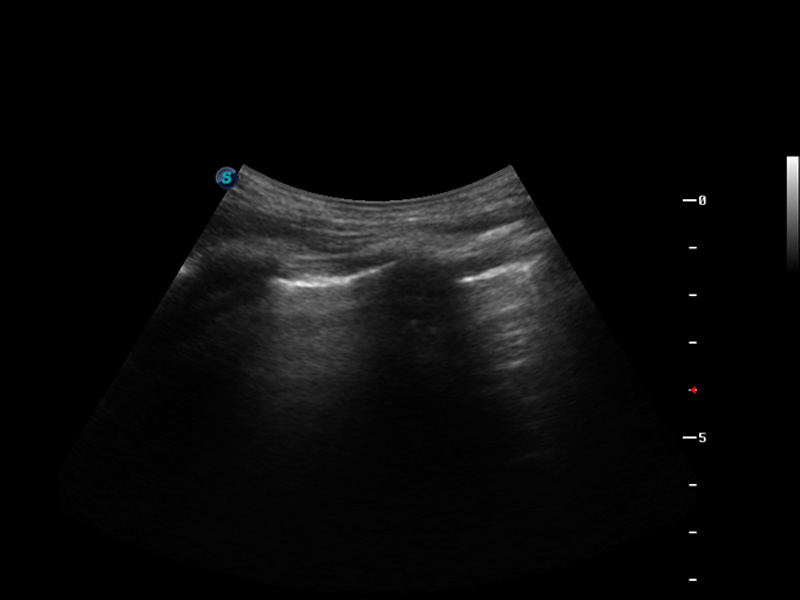

S9便携式彩色多普勒超声诊断仪是16877太阳集团研发的高端便携彩超设备,外观设计新颖、产品性能卓越。S9在便携超声领域采用了突破传统的触摸屏交互设计,并以先进的软件硬件技术和设计理念,为您带来清晰的图像质量、稳定的工作性能和便捷的操作体验。